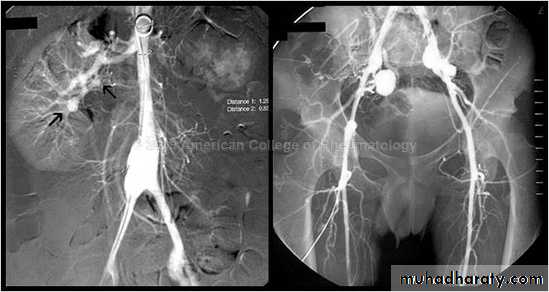

Angiography of abdominal aortic aneurysm

CT & CT angio of abdominal aortic aneurysm

MRI of abdominal aortic aneurysm